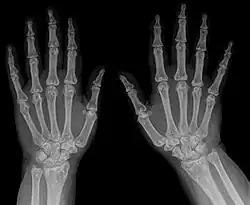

| Diagnostic method | X-ray, ultrasound[3] |

- X-ray